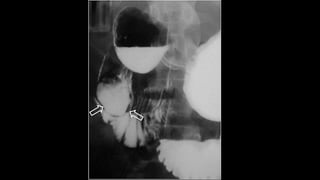

SIGNO DE LA MEDIA

LUNA O DEL MENISCO

• Signo de invaginación intestinal

en la radiografía simple de

abdomen.

• Corresponde a la semiluna de

gas intraluminal que queda

atrapado entre el asa

invaginada y el asa invaginante.

• En el enema opaco, se forma

por el bario que rellena el

colon hasta el ángulo opaco.

• El defecto de repleción

redondeado corresponde a la

cabeza de la invaginación.

Alrededor se acumula en bario

con forma semilunar.

SIGNO DE LAMEDIA LUNA O DEL MENISCO • Signo de invaginación intestinal en la radiografía simple de abdomen. • Corresponde a la semiluna de gas intraluminal que queda atrapado entre el asa invaginada y el asa invaginante.

• En elenema opaco, se forma por el bario que rellena el colon hasta el ángulo opaco. • El defecto de repleción redondeado corresponde a la cabeza de la invaginación. Alrededor se acumula en bario con forma semilunar.